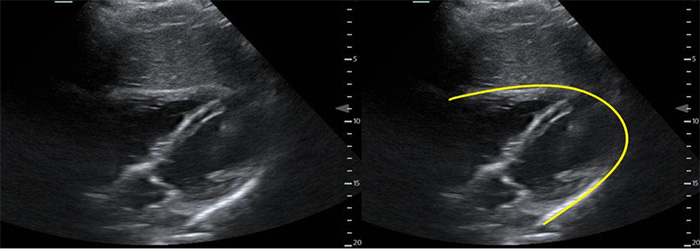

- With the transducer in the subxyphoid region, transducer in the transverse plane, evaluate the periaortic region for large lymph nodes. (Figure 1, #2)

- Identify the arch of the vertebral body in the far field then the aorta just to the patient’s left.

- Identify the “seagull sign” of the celiac trunk and slide the transducer inferiorly to the bifurcation of the common iliac arteries.

- Normally, lymph nodes will be difficult to visualize because they are small and normally hypoechoic with a hyperechoic central hilum. As they enlarge, the architecture is distorted, and they develop a homogeneous echotexture. Attempt to image lymph nodes in 2 planes and measure the diameter.

Figure 3. Proximal aorta (A) with celiac trunk "seagull sign" (*) adjacent to the IVC and vertebral body (V)